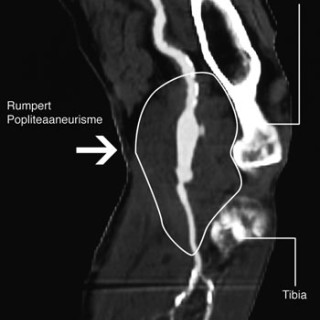

En 23 år gammel førstegangsgravid kvinne som fra tidligere stort sett var frisk, ble innlagt i lokalsykehus ved svangerskapslengde 22 uker + 2 dager, med en seks dagers sykehistorie med generell sykdomsfølelse, feber opptil 40 °C, kvalme, oppkast og anoreksi. I tillegg hadde hun fått økende ansiktsødemer, korsryggssmerter, hodepine og synsforstyrrelser. Svangerskapet hadde vært ukomplisert frem til det aktuelle. Hun var normotensiv. Blodprøvene viste kreatinin 236 µmol/l, karbamid 13 mmol/l, urat 410 µmol/l, leukocytter 15,0 · 10⁹/l, CRP 106 mg/l og trombocytter 86 · 10⁹/l. Leverprøvene var...